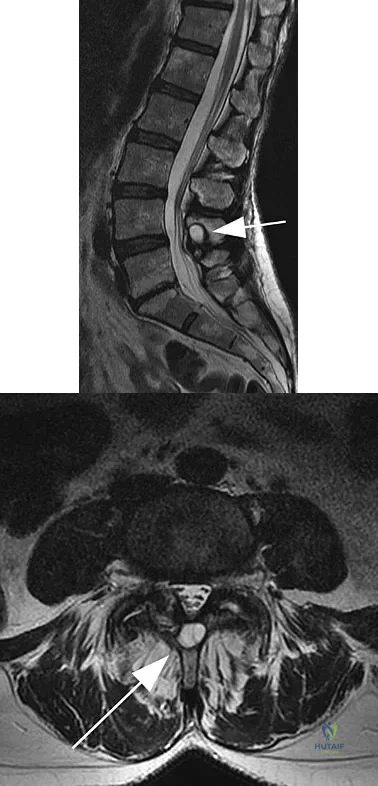

Question 1

A 38-year-old man reports a 2-week history of acute lower back pain with radiation into the left lower extremity. There is no history of trauma and no systemic signs are noted. Examination reveals a positive straight leg test at 35 degrees on the left side and a contralateral straight leg raise on the right side. Motor testing demonstrates mild weakness of the gluteus medius and weakness of the extensor hallucis longus of 3+/5. Sensory examination demonstrates decreased sensation along the lateral aspect of the calf and top of the foot. Knee and ankle reflexes are intact and symmetrical. Radiographs demonstrate no obvious abnormality. MRI scans show a posterolateral disk hernation. The diagnosis at this time is consistent with a herniated nucleus pulposus at

Figures 11a and 11b show the T2-weighted MRI scans of the lumbar spine of a 53-year-old woman who has low back and right lower extremity pain. What structure is the arrow pointing to in Figure 11a?

A 19-year-old man has had back pain with activity, especially running in soccer and baseball, for the past 4 months. He denies any history of trauma. Examination reveals no motor weakness or sensory changes in the lower extremities. Range of motion shows increased pain with extension and mild limitation with flexion. A sitting straight leg raising test is limited at approximately 60 degrees bilaterally by back and buttocks pain. Plain radiographs are normal. MRI scans are shown in Figures 13a through 13e. What is the most likely diagnosis?

Explanation